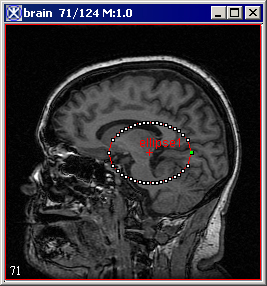

The pointer changes to the cross-hair shape. As you move the pointer, MIPAV determines the level of intensity of the pixel under the cross-hair pointer and uses the results from the Levelset algorithm to determine the probable boundary of the structure. Having determined the probable boundary, MIPAV generates a contour (Figure 1). Continue to move the pointer until the structure you wish to outline is contoured.

3 Click the contour to apply it to the structure. See Figure 1.

Figure 1. Automatically generated contour.